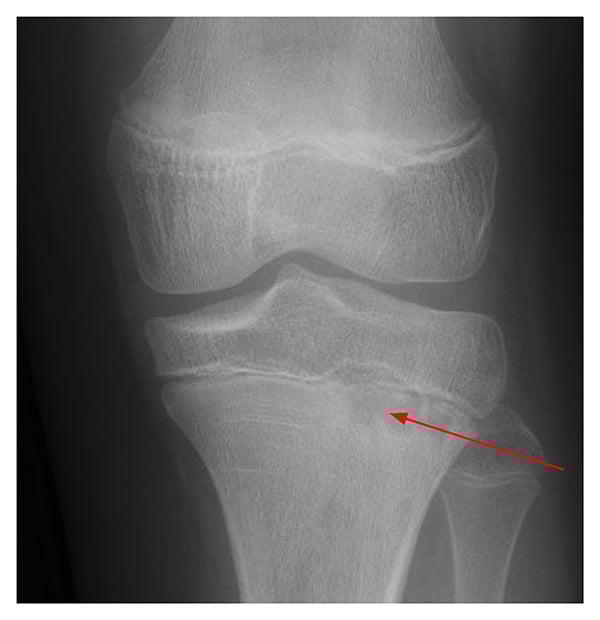

At her initial rheumatology visit, she also reported pain in the left knee and back. X-ray of the left knee revealed a metaphyseal lucency at the lateral tibia with mild surrounding sclerosis (Fig. 2). Whole-body MRI showed multiple metaphyseal regions of bone marrow edema lesions, with erosions of the left knee and right ankle consistent with CNO. Upper thoracic vertebral lesions were also found (Fig. 3).

Figure 2: Knee X-ray shows lateral tibia metaphyseal lucency with surrounding sclerosis.